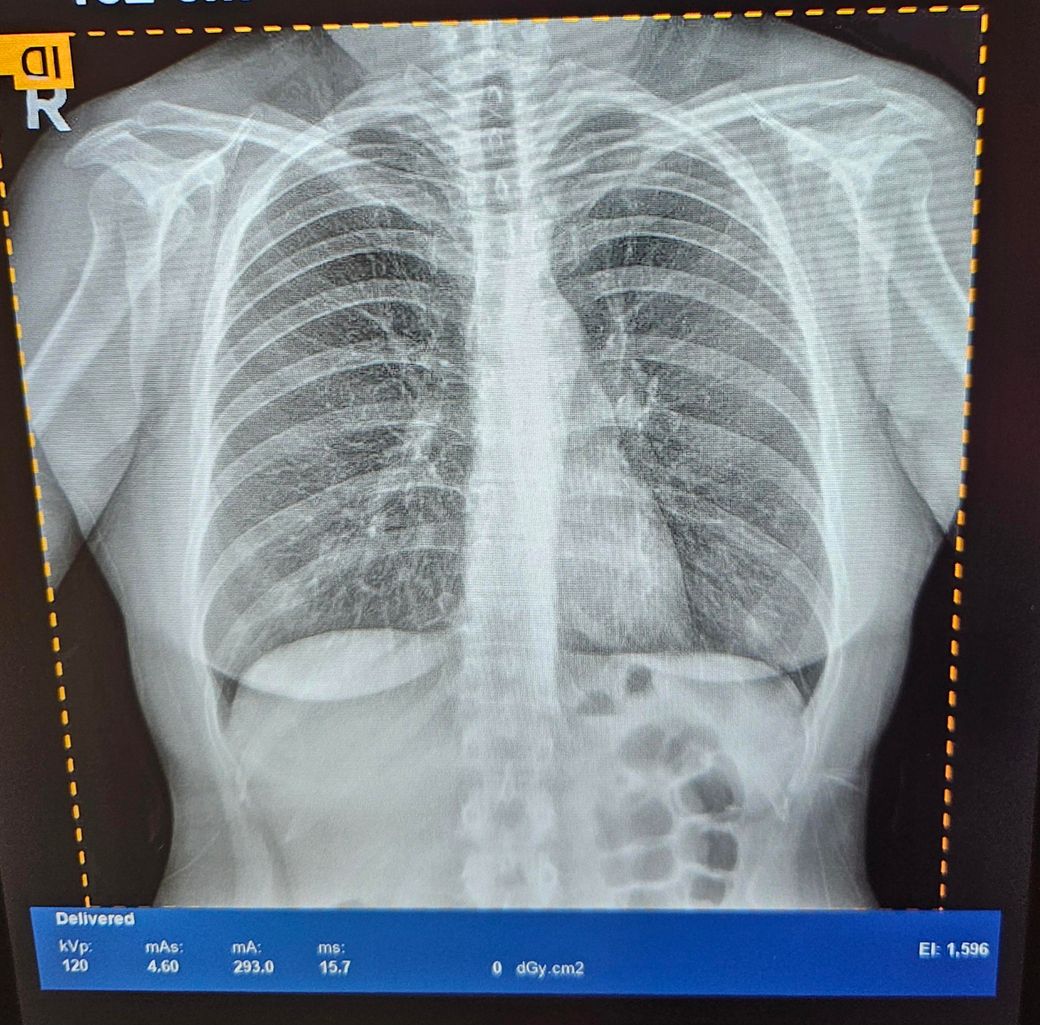

폐엑스레이에서는 기관지가래나 기관지확장증같은건 확인안되나요?

기관지에 가래가 있다는 소견을 받았는데요

액스레이에서는 기관지 확장증이나

가래여부가 확인이 안될까요?

그리고 인터넷에 많은 다른 엑스레이 사진들보다

제 사진이 전체적으로 뿌얘요ㅠㅠ

왜그런건가요?

엑스레이로 가래 혹은 기관지 확장증을 확인하려면 병변이 심하거나 자료의 quality가 우수해야 합니다

지금처럼 화면을 핸드폰으로 찍은 사진의 경우 quality가 아무래도 불량하기 때문에

파일을 다운받으시면 조금더 좋은 화질을 얻을 수 있습니다.

환자분 사진이 전체적으로 뿌연것도 같은 맥락으로 이해하시면 됩니다

폐xray나 ct촬영등을 통해 기관지확장증을 진단할수 있습니다 엑스레이 사진이 뿌옇게 나오는것도 기관지확장증의 소견일 가능성이 있습니다